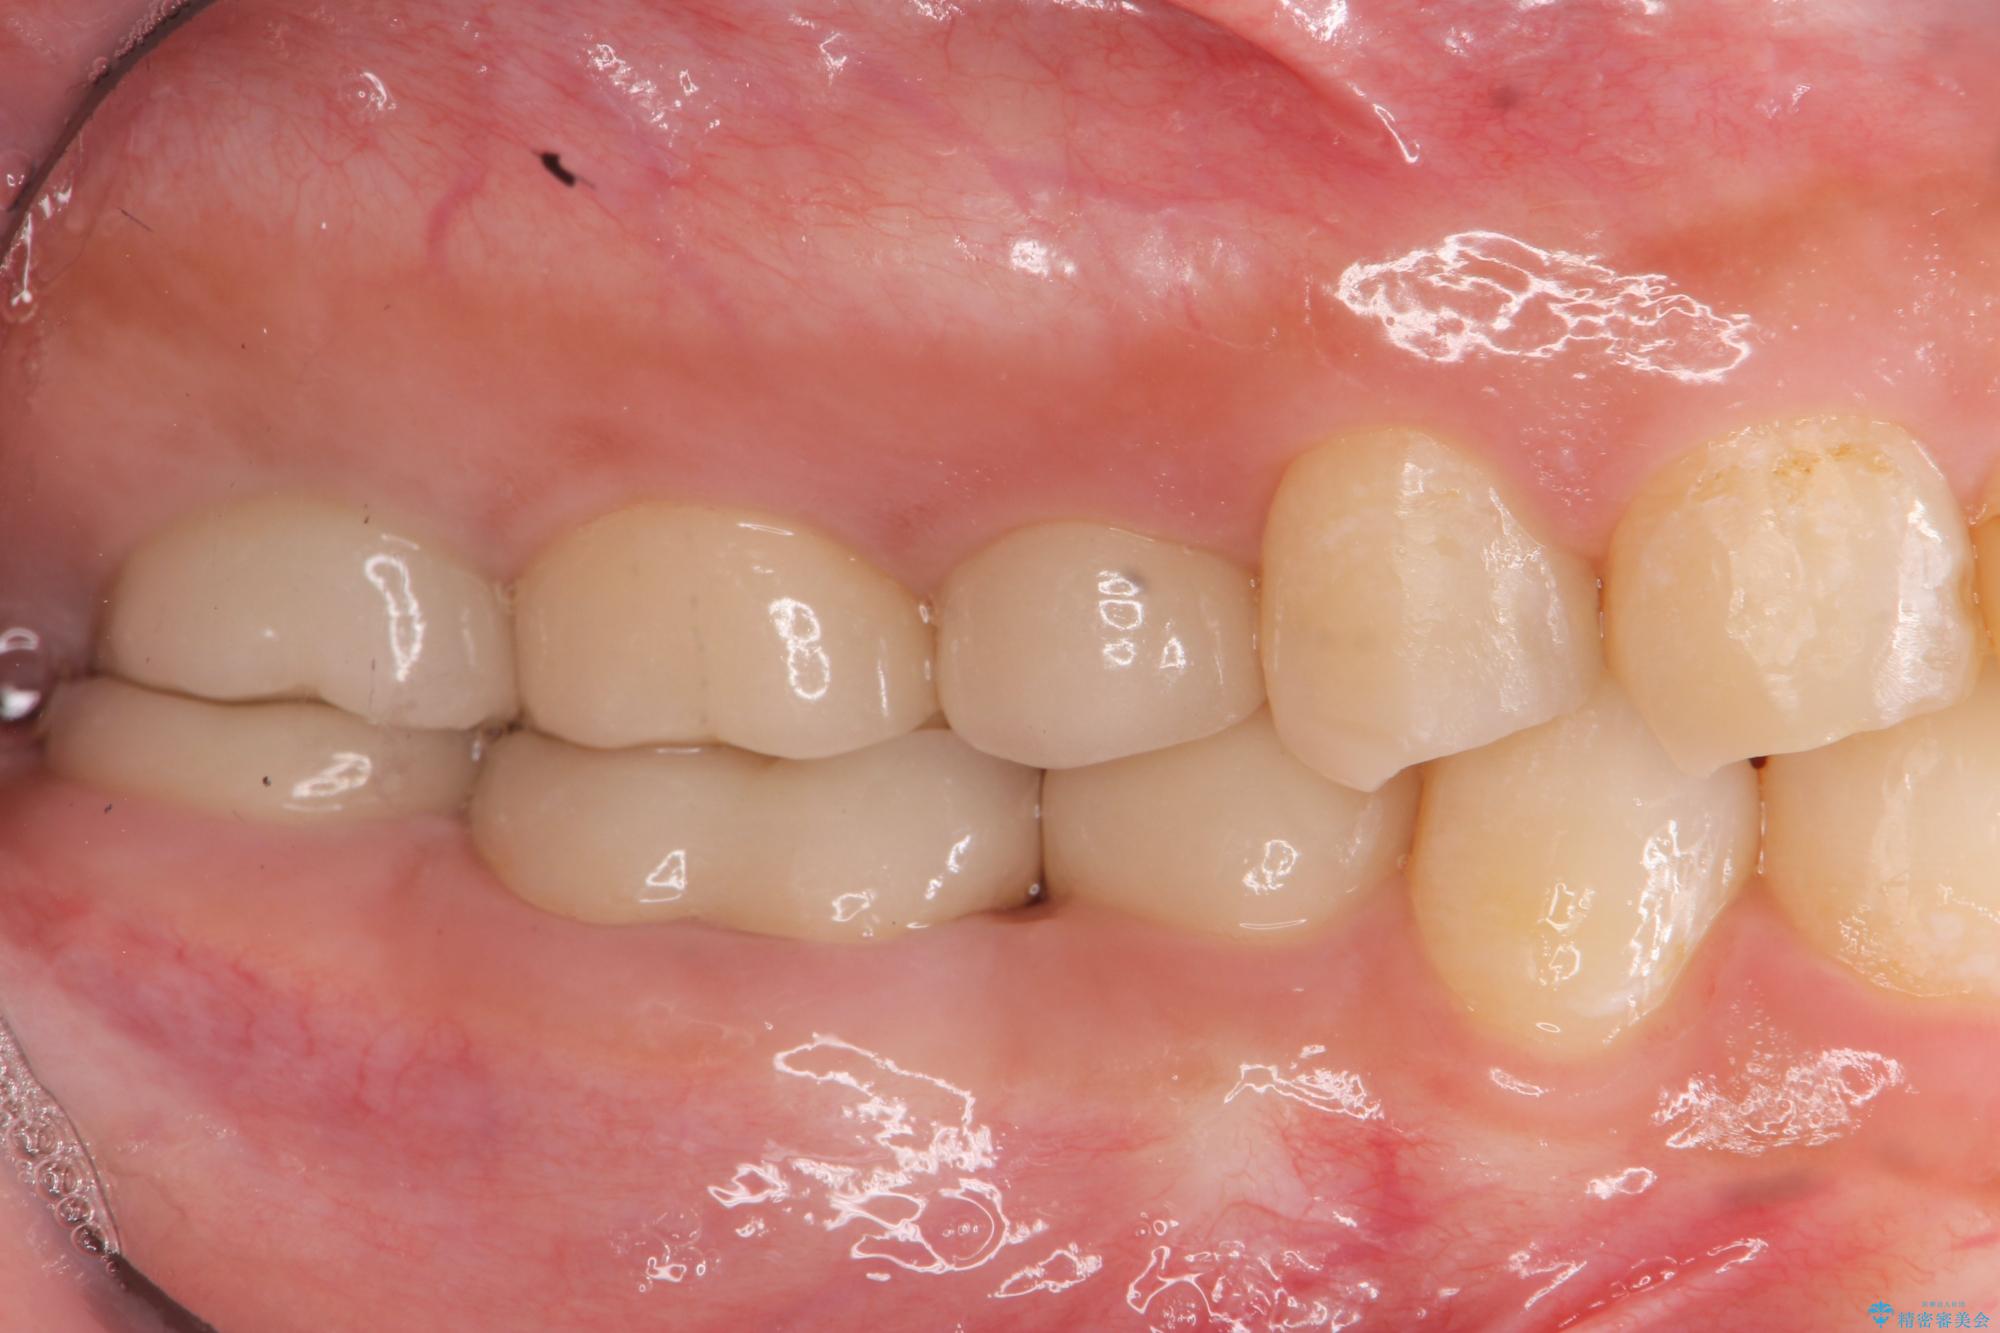

- 治療途中で放置してしまった奥歯の治療の続きを希望され来院されました。

奥歯は既に根管治療が為されクラウンを装着する必要性がある状態ですが、歯の高さが低くクラウンの安定性・強度を担保するために歯周外科を行う治療計画としました。

歯周外科を行うことで、歯ぐきの位置を下げ歯の高さを作り出し安定したクラウンの装着が可能となります。また同時に舌の邪魔となっていた骨隆起の除去を行うこととしました。